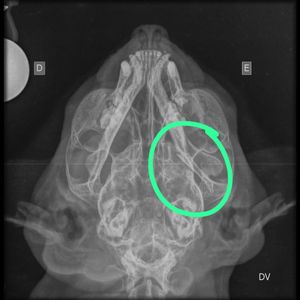

me chamo yasmin sou a irmã humana da sol, criei esta campanha para a cirurgia da mandíbula dela que infelizmente foi quebrada por cachorros..

eles a atacaram por causa de um descuido do meu avô de deixar o portão aberto. morderam a barriguinha dela e a parte íntima dela, e quabraram a mandíbula dela!😔

já levamos ao veterinário porém gastamos um valor avaliando a 2 mil, e não temos mais 1440 para a cirurgia da mandíbula, por isso peço a contribuição de vocês, qualquer valor ajuda.